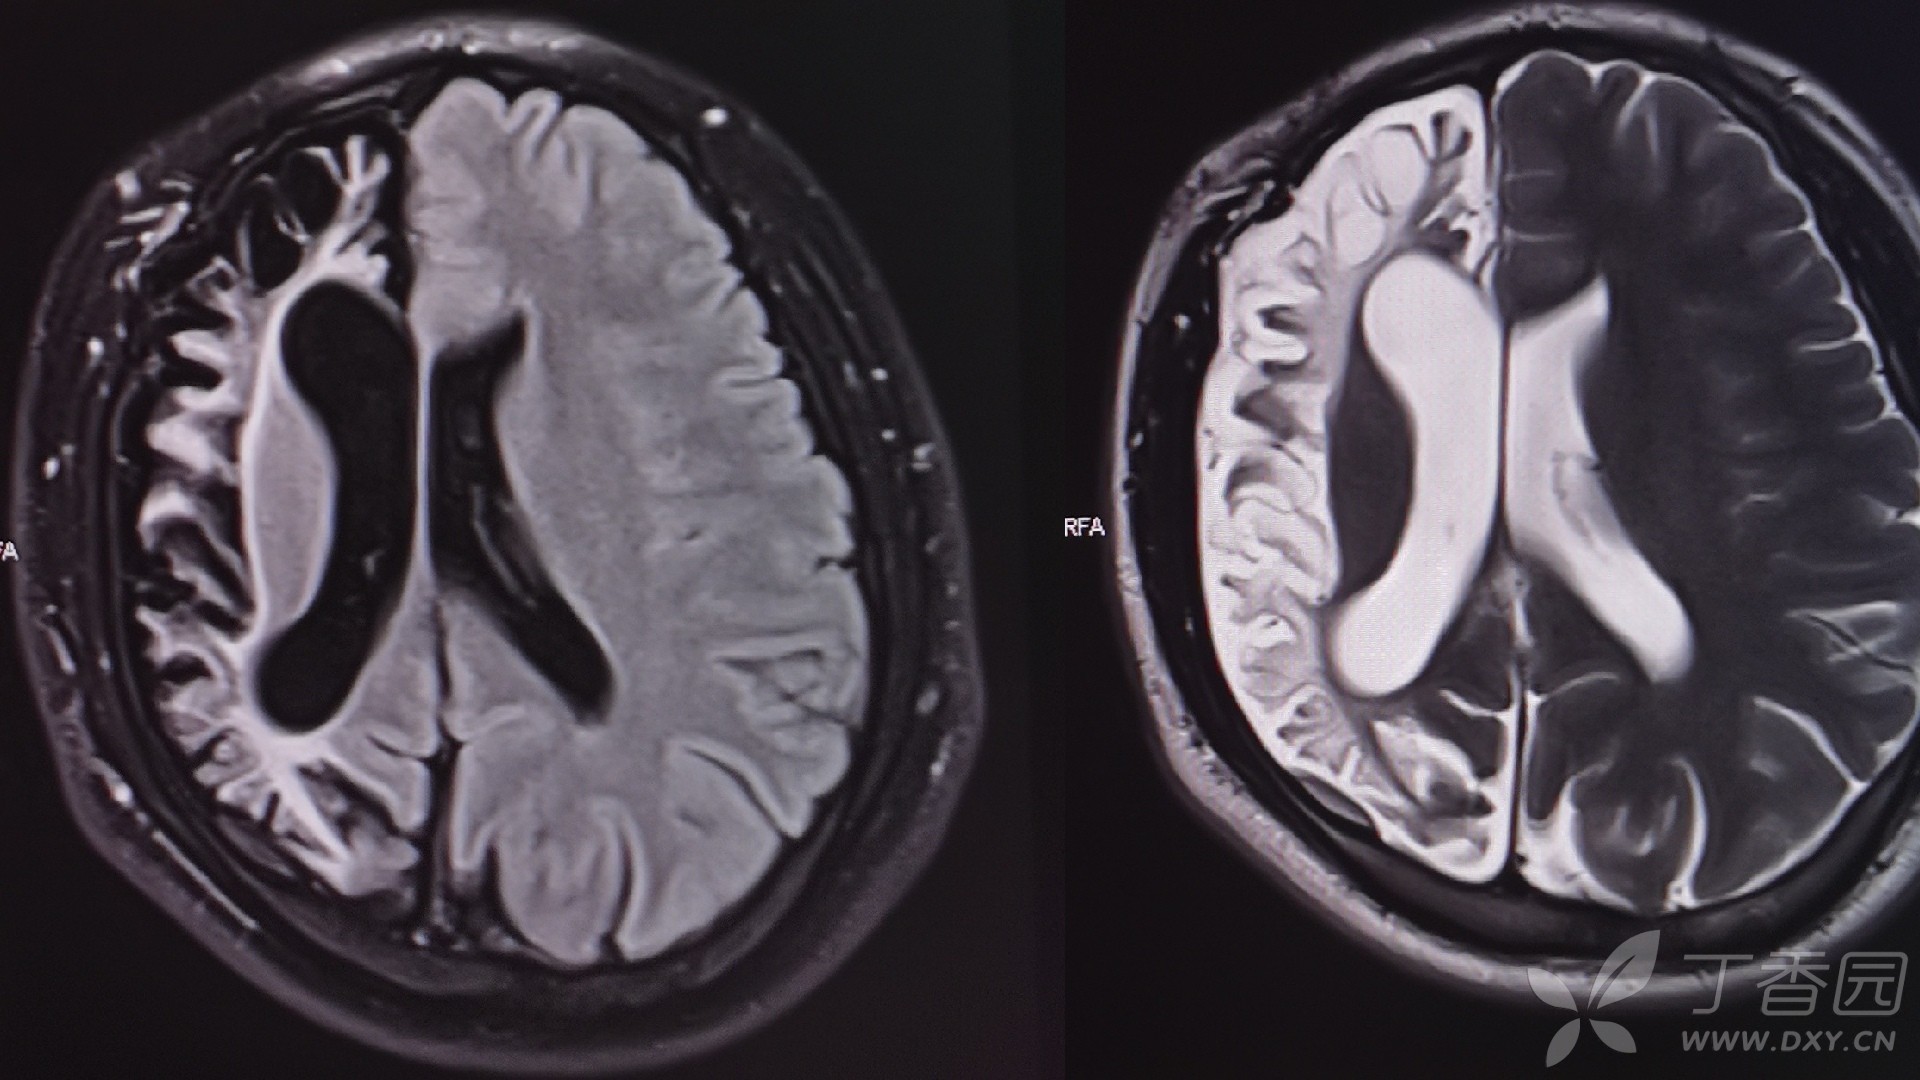

今天碰到一例Rasmussen脑炎,请看图:

影像学

MRI已成为诊断及评估RE预后的一个不可或缺的依据,其特征性表现为单侧脑沟、脑回及侧脑室扩大,皮层及皮层下脑白质在T2/FLAIR上高信号,基底节尾状核头部轻、重度萎缩。通常,急性期MRI显示单侧半球萎缩,最先由颞叶岛盖开始,伴有颞角萎缩,侧裂扩大。皮质萎缩常在单侧额岛叶进行性发展,通常累及额叶、岛叶、额岛叶、额颞岛叶、顶颞岛叶和额顶-枕岛叶。正电子体层扫描(PET)通常会显示患侧半球脑代谢降低。单光子发射计算机断层呈像术(SPECT)可在早期观察到病变范围的扩展,可见患侧半球脑代谢降低,其显示的病灶范围更为广泛,对RE的病灶定位有重要意义。